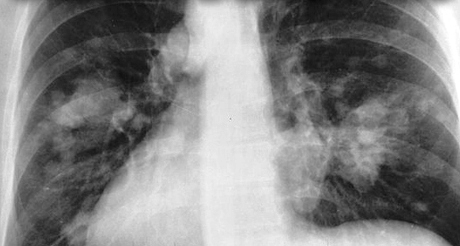

Smog, ground-level ozone, causes a host of respiratory consequences, ranging from coughing, wheezing and throat irritation, to asthma, increased risk of infection, and permanent damage to lung tissue.

Via the Guardian, 2016 / “We have a public health emergency in many countries from pollution. It’s dramatic, one of the biggest problems we are facing globally, with horrible future costs to society,” said Maria Neira, head of public health at the World Health Organization. “Air pollution leads to chronic diseases which require hospital space. Before, we knew that pollution was responsible for diseases like pneumonia and asthma. Now we know that it leads to bloodstream, heart and cardiovascular diseases, too – even dementia. We are storing up problems. These are chronic diseases that require hospital beds. The cost will be enormous.”

Smog lung-damage2.jpg